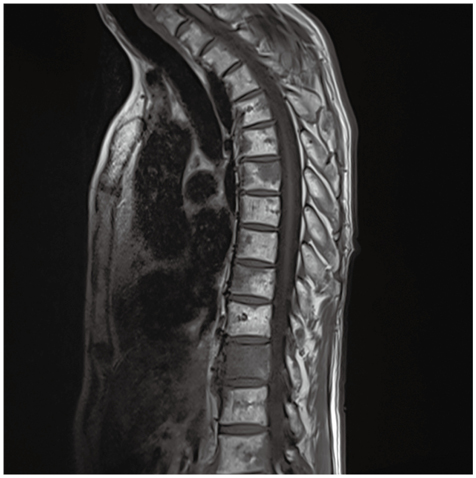

T1強調像で椎体に多発する低信号域!診断は……?[Similar but Different〜画像診断報告書(18)]

症例1

症例1の患者情報

60歳代,男性。

仕事中に尻もちをつき受傷。胸腰椎MRI検査で異常を指摘された。

既往歴:悪性腫瘍なし。腰部脊柱管狭窄症,高血圧症。

生活歴:飲酒は発泡酒1500mL/日。食事は肉,魚,野菜はほとんど摂らず,炭水化物中心。